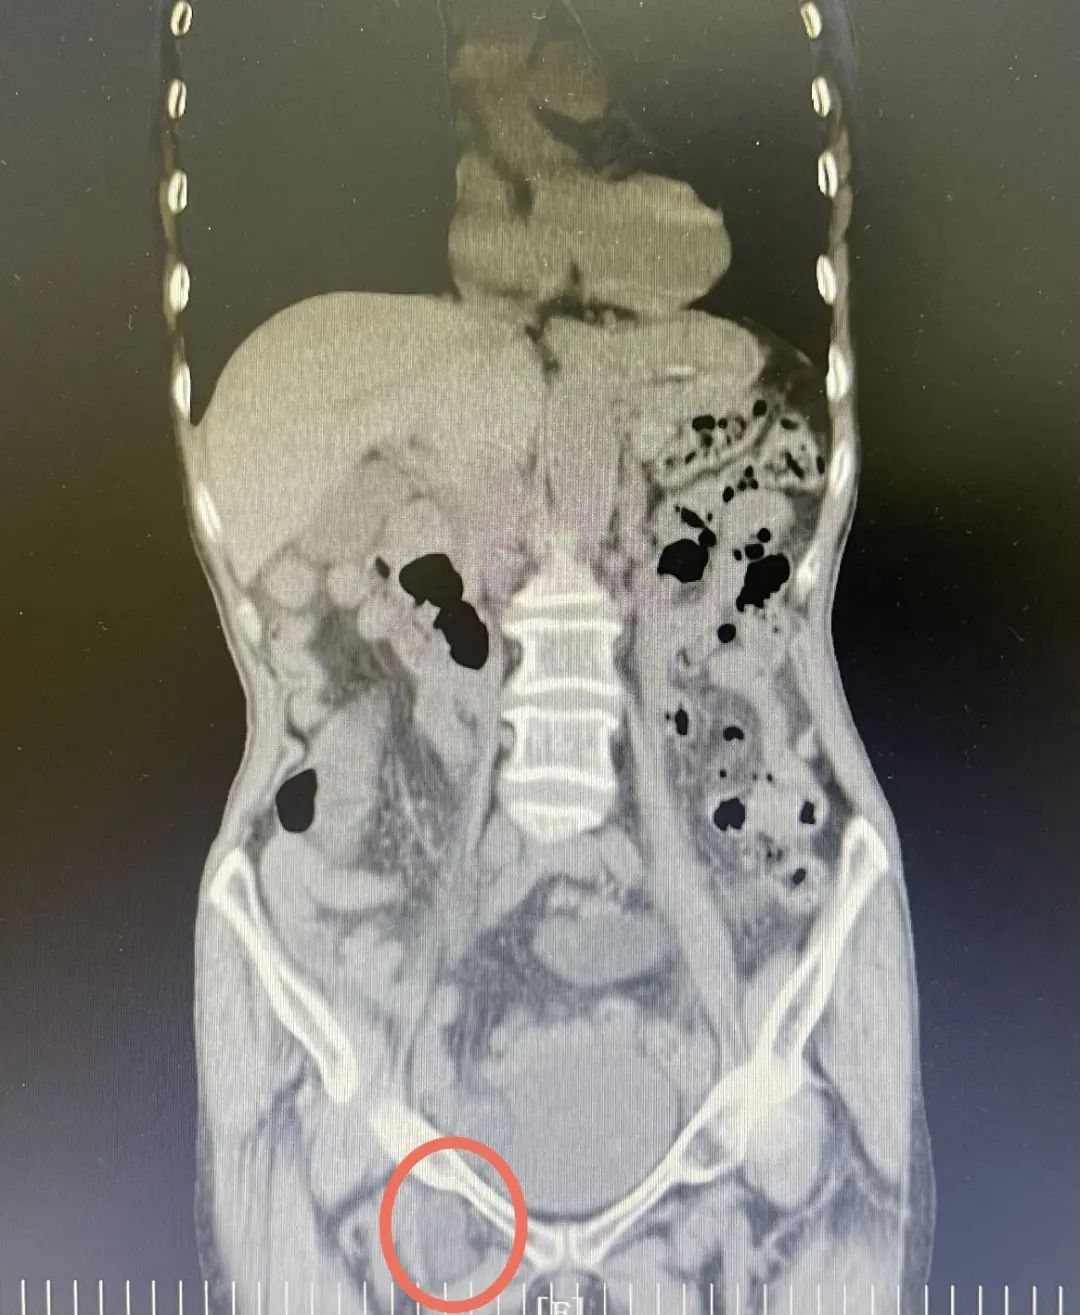

右腹股沟区肿块合并回盲部占位!